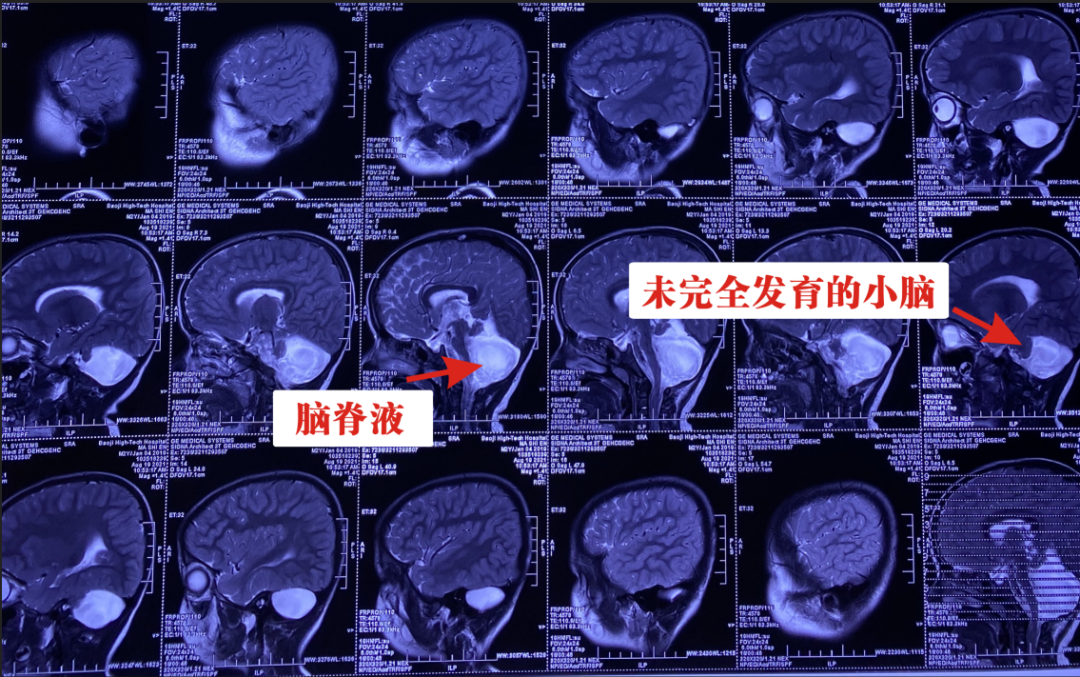

病例:孩子今年2岁7个月,1年前发现孩子语言发育迟缓,只能单音发某个字,只有家人搀扶才能走路,行走时左腿步幅较大,右腿稍拖拉,自主站立较困难,曾四处寻医治疗,未见好转。 在我院做核磁共振提示:中枢欠对称,左侧较小,小脑形态小,双侧不对称;枕大池明显扩大,考虑发育畸形,诊断:先天性脑发育异常,收住神经外科。